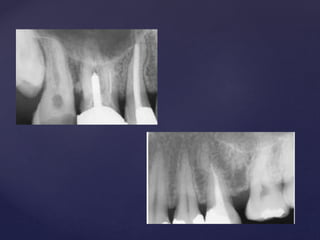

Types according to it’s morphology

1. Apical

2. Middle

3. Coronal

4. Combination

Types according to it’s location

Apical

Coronal

Middle